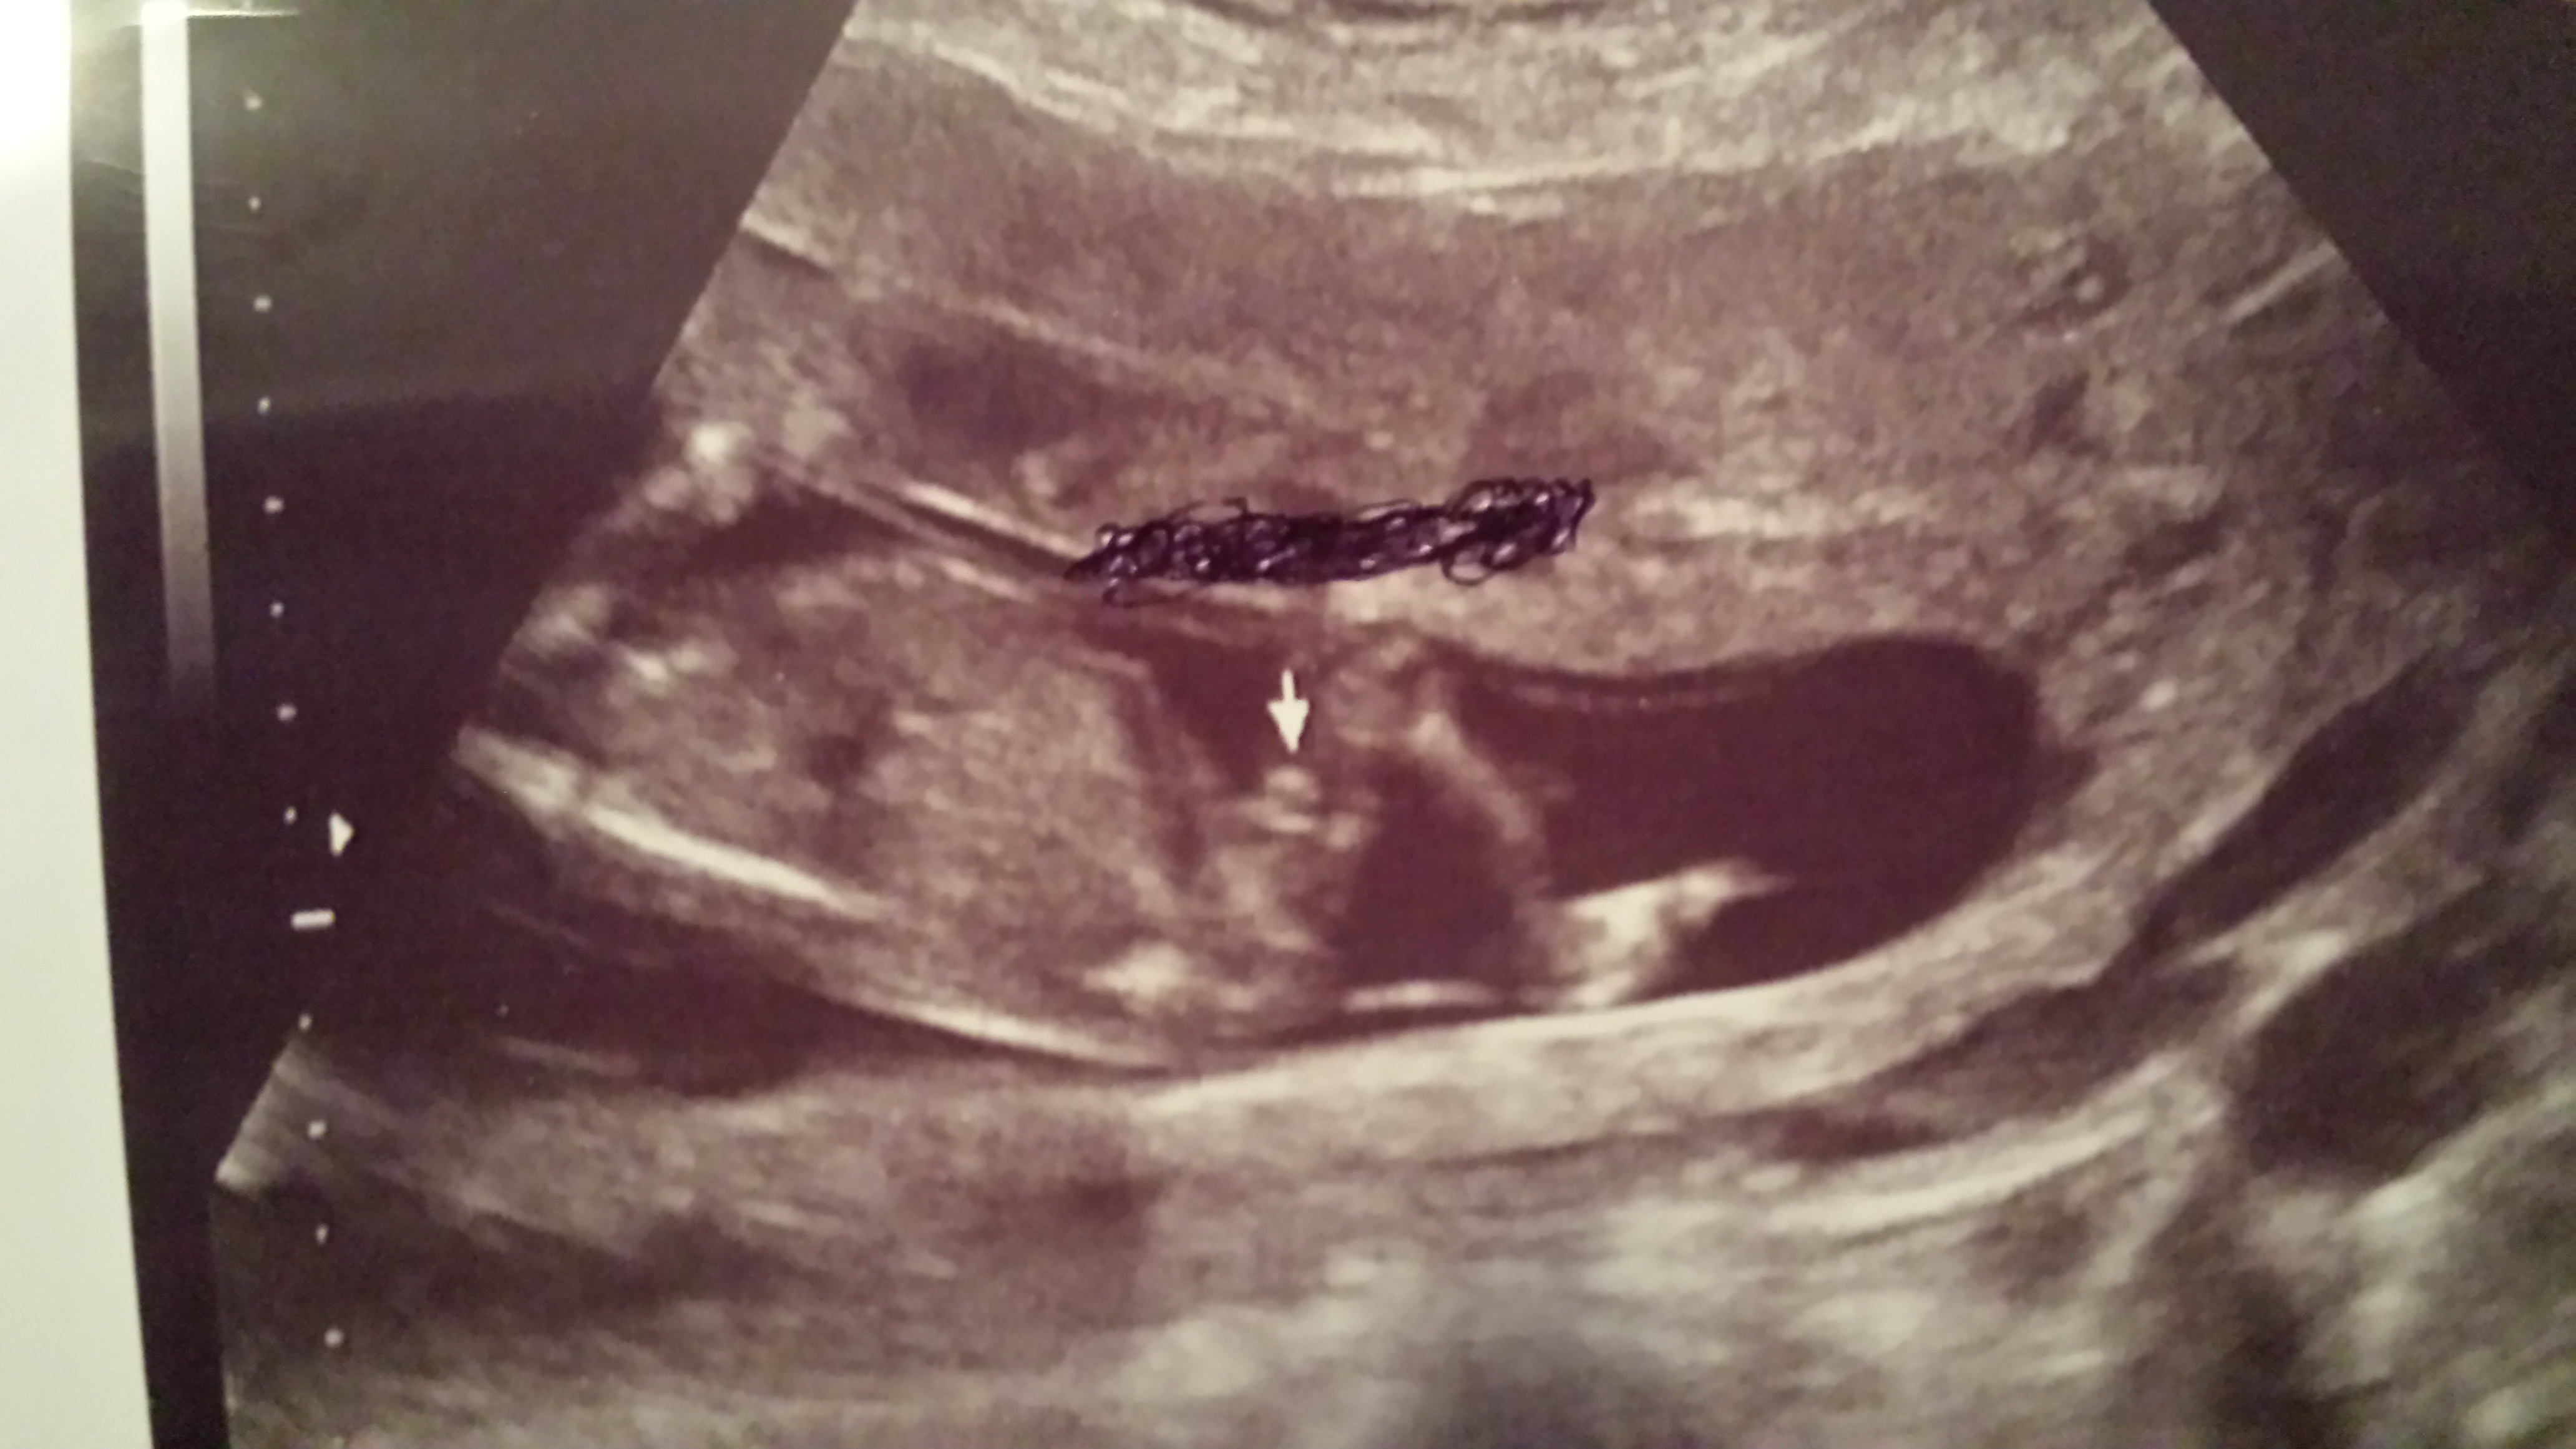

Maybe boy.

want to know so bad :) hopefully next time I am at the dr they will be able to confirm

looks boyish

i would say boy...due to similarity i see on my previous boys...

Looks like a nice boyish shot.